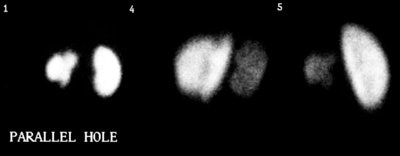

The recommended minimum dose is 0.3 to 0.4 mCi of Tc-DMSA, with a maximum dose of 3 mCi (110 MBq). Imaging is performed 2 to 3 hours after injection and should include a posterior view, acquired for 300,000-500,000 counts or 5 minutes using a high-resolution parallel-hole collimator [11]. A posterior oblique view should also be acquired [11]. Pinhole images are then acquired using a 3-4 mm aperture for 100,000-150,000 counts or for 10 minutes [11]. SPECT images detect more defects, but are technically demanding, often require sedation, and offer no statistically significant advantage [6]. A recent report [7] showing SPECT defects in normal volunteers suggests specificity may decrease significantly with SPECT imaging. A study in piglets demonstrated slightly greater sensitivity, but lower specificity and equal accuracy for SPECT when compared with pinhole imaging [8]. For a detailed description, see SNM Nuclear Medicine Procedure Guidelines for Renal Cortical Scintigraphy in Children (June 1996). The estimated radiation dose to the kidneys (target organ) of a one year old child from 99m-Tc-DMSA is 0.78 mGy/MBq administered dose. A standard dose is about 1.85 MBq/kg (50uCi/kg). The radiation dose is therefore about 14.4 mGy (which is lower than that of spiral CT) [10].

Differential renal functions are calculated from the parallel hole posterior image. When there is a significant depth discrepancy between the two kidneys, anterior and posterior images should be acquired and a geometric mean determined. The lowest normal value of relative uptake is 45% [11]. A greater than 10% difference in uptake between the two kidneys is considered abnormal [11]. Hydronephrosis may cause a problem with image interpretation because of tracer retention within the collecting system [11].